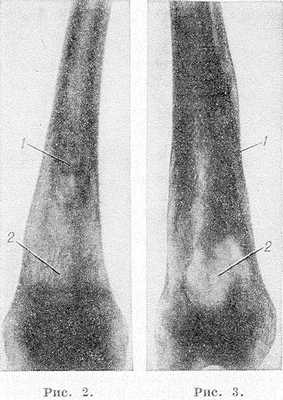

Рис. 2 и 3. Рентгенограммы бедер при болезни Гоше. Рис. 2. Булавовидное расширение метадиафиза бедренной кости в нижней трети с выраженными внутрикостными обызвествлениями (1) и широкопетлистой костной структурой (2). Рис.З. Расширение метадиафиза бедренной кости с уплотнением (1) и обширным участком деструкции (2).

Наиболее часто изменения обнаруживают в длинных трубчатых костях и позвоночнике. Первое место по частоте поражения занимает дистальная половина бедра, где выявляют характерное веретенообразное или булавовидное вздутие кости (рис. 2 и 3) с истончением коркового слоя, к-рое часто сочетается с грубоячеистой структурой, внутрикостными обызвествлениями, отдельными очагами деструкции и иногда с эностальным склерозом кости. Периостозы, как правило, не развиваются; иногда могут наблюдаться обширные краевые деструкции, сопровождающиеся периостозами. В головке бедренной кости образуются асептические некрозы по типу болезни Пертеса со свойственной данному заболеванию стадийностью процесса и исходами (см. Пертеса болезнь). Может наблюдаться утолщение шейки бедра (рис. 4) с образованием coxa vara.